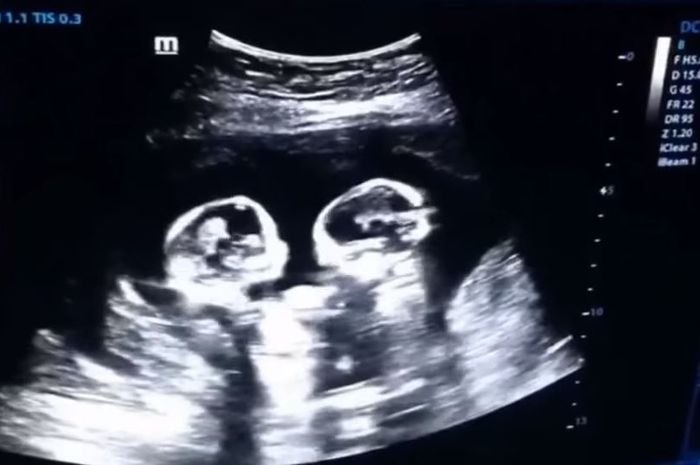

Penggerebekan yang tidak terduga mengungkap kisah mengerikan di sebuah apartemen di Kota Malang. Dua janin bayi kembar laki-laki ditemukan dalam kondisi yang menyedihkan, berada di dalam bak penampungan septic tank. Kejadian ini memicu kegundahan dan pertanyaan besar tentang bagaimana dua bayi itu bisa sampai ke tempat tersebut.

Janin yang ditemukan pada Jumat (6/2/2026) pukul 16.00 WIB, masih memiliki tali pusar yang menempel. Saat ditemukan, kedua jasad itu langsung dievakuasi ke Rumah Sakit dr Saiful Anwar (RSSA) Kota Malang untuk pemeriksaan lebih lanjut. Penemuan ini terjadi setelah petugas engineering apartemen bersama vendor sedot WC melakukan pembersihan sistem limbah air kotor.